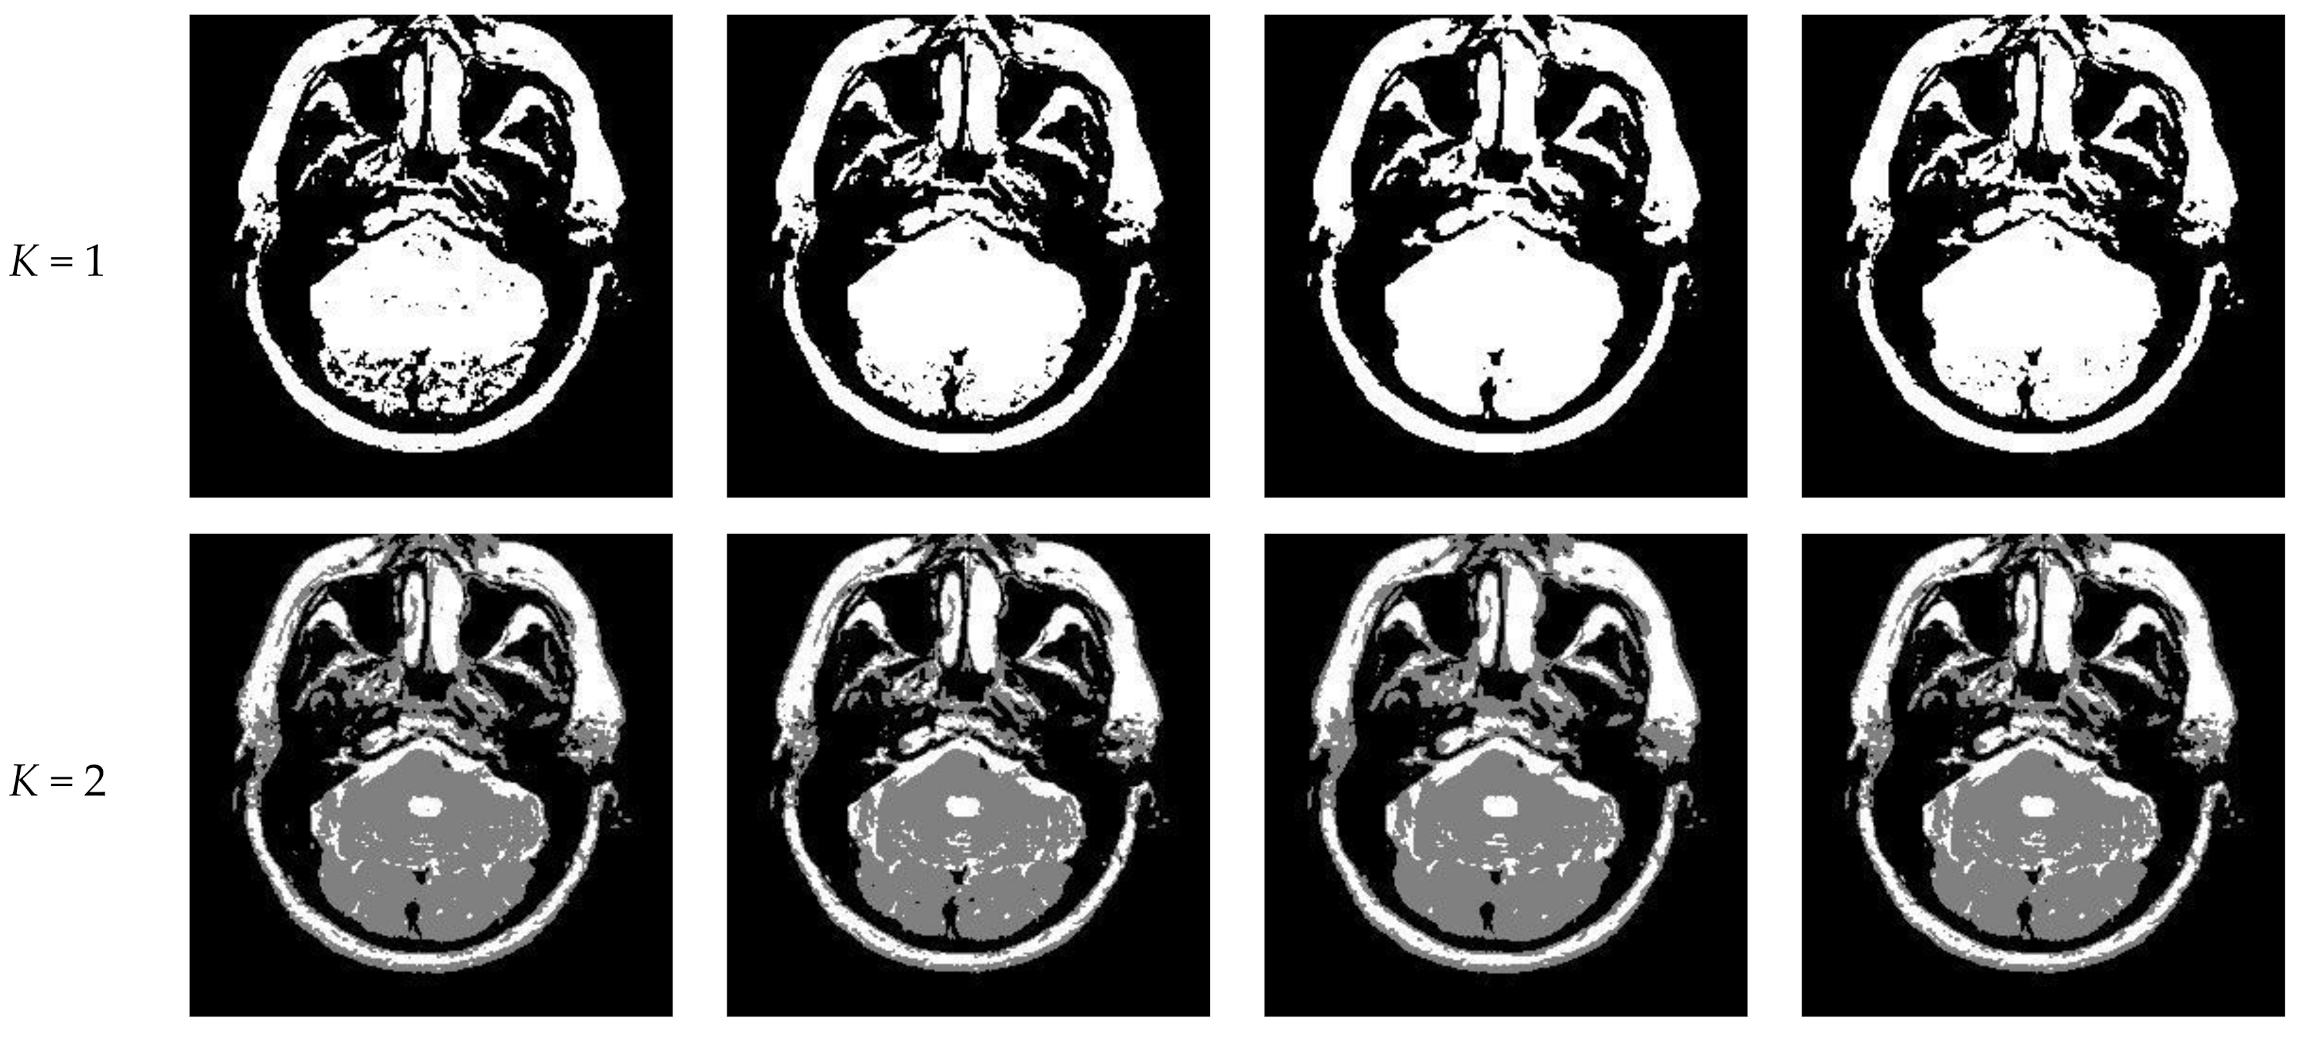

Figure 10 and Figure 11 display segmentation results of different algorithms for slice #042 and slice #082, respectively. For single level of thresholding K = 1, it can be observed that segmentation results obtained by the Otsu method have many fragmented small areas, such as the lower soft tissue in the first row of Figure 10a, whereas IIMT performs slightly better. However, the edges segmented by HL-IIMT and Proposed are much clearer. In the case of , it can be seen that Otsu and IIMT have similar segmentation effects. HL-IIMT and Proposed are better than Otsu and IIMT in terms of edge-preserving and denoising, as shown in the segmentation results in Figure 11 (K = 2, K = 4).

Figure 10.

Segmentation results obtained by different segmentation algorithms for slice #042 with number of thresholds K from 1 to 5: (a) Otsu, (b) IIMT, (c) HL-IIMT, (d) Proposed.

Table 2 shows the values of uniformity measure (U) of Proposed, HL-IIMT, IIMT, and Otsu algorithms for slice #042 and slice #082. The best evaluation results are marked in bold. It can be noted that the U values achieved by Proposed are the highest for both of the two test images. To more clearly present the results, Figure 12 illustrates the comparison of U for different algorithms based on Table 2. In Figure 12, it can be clearly noted that Proposed achieves the highest values, and HL-IIMT comes second, followed by IIMT and Otsu. This indicates that the novel thresholding method IIMT presented in this paper is effective, and our Proposed based on IIMT can obtain satisfactory segmentation results with clear edges and little noise.